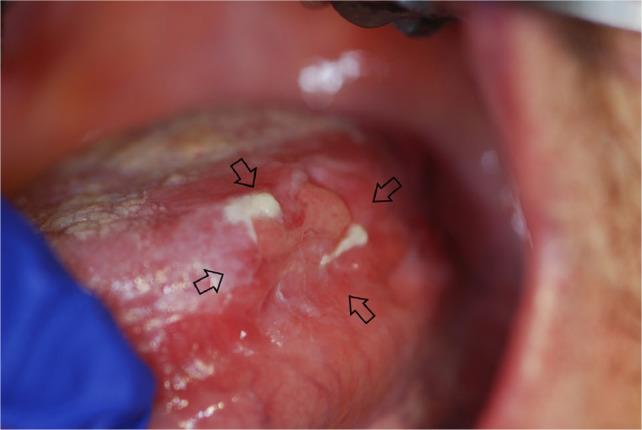

Acute GVHD may manifest in the oral mucosa; however, it often develops immediately following HSCT when routine dental treatment is postponed. Chronic GVHD may manifest in the oral mucosa, the salivary glands and the musculoskeletal compartment. It may indirectly affect the teeth and the oral flora, putting the patient at risk for infections. Importantly, GVHD poses an increased risk for oral cancer.

急性 GVHD 可能在口腔黏膜中表现出来;然而,它通常在 HSCT 后立即发生,此时常规的牙科治疗被推迟。慢性 GVHD 可能在口腔黏膜、唾液腺和肌肉骨骼部位表现出来。它可能会间接影响牙齿和口腔菌群,使患者面临感染的风险。重要的是,GVHD 增加了口腔癌的风险。